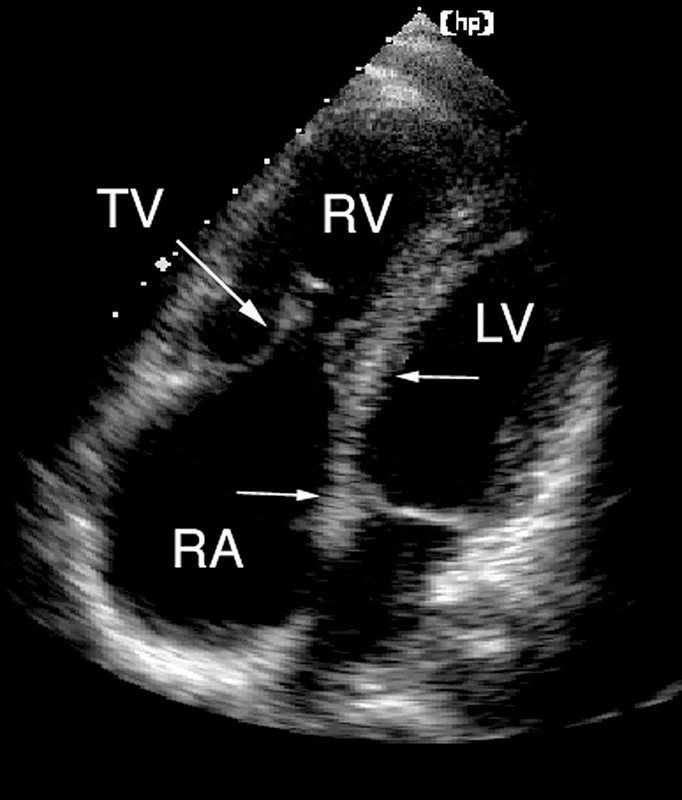

فحوصات تشخيصية لبعض امراض القلب والشرايين التاجية